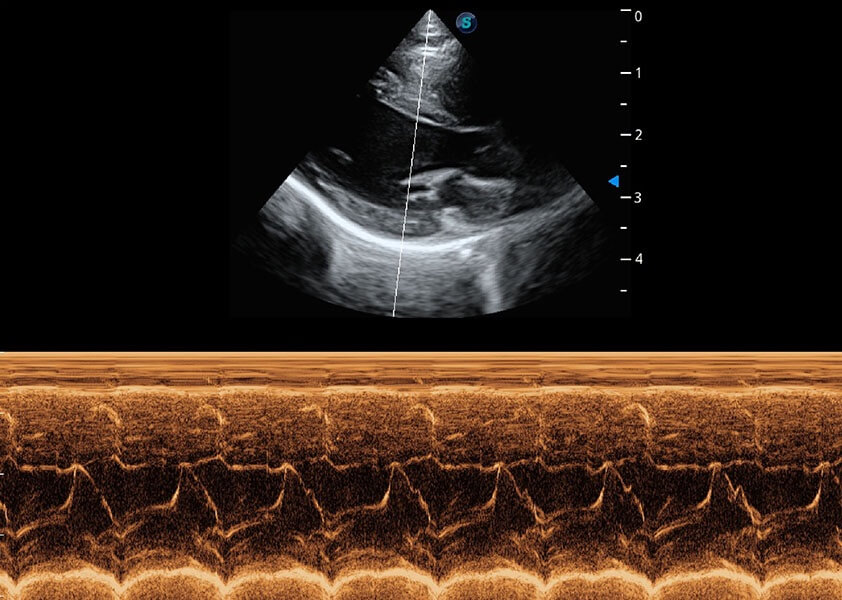

• AMM 解剖M型

通过360度任意调节3条M型取样线,在同一心动周期上观察心脏不同位置的运动曲线,得到准确的心功能测量数据,有效评估心肌运动及左心室功能。

(犬)心脏组织多普勒